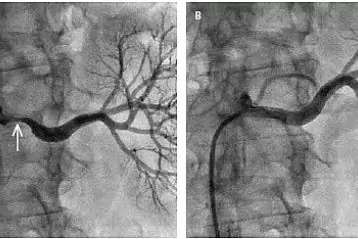

Récemment, mon travail se concerte sur une méthode innovante de la lutte contre l'ischémie, qui provoque déjà une véritable révolution dans le monde. Je pense qu'il s'agit d'une véritable avancée dans la médecine naturelle, utilisée depuis des années dans le domaine de l'angiologie.

Des recherches effectuées ont démontré que l'action des ingrédients contenus dans la formule Cariovico fait baisser presque immédiatement le "mauvais" cholestérol, donc sa fraction LDL, tout en normalisant le métabolisme de glucoses et de lipides de l'organisme. Grâce à cela, Cariovico minimise le dépôt de plaques d'athérosclérose dans les artères.

Restaurer le bon profil sucre-graisse dans le corps est extrêmement important, mais ce n'est pas tout. Cariovico a la capacité de ramollir, de desserrer et - enfin - de dissoudre progressivement les dépôts dangereux accumulés au fil des années dans les vaisseaux sanguins. Ils sont évacués du corps en toute sécurité.

Cariovico agit sur plusieurs niveaux. En plus de permettre à l'organisme de retrouver son équilibre biochimique il dégage les vaisseaux artériels bloqués par les lipides. De plus, il tonifie et renforce les tissus délicats des vaisseaux sanguins, améliorant leur état et prévenant le gonflement.

Grâce à des ingrédients soigneusement sélectionnés et concentrés au maximum, les parois des vaisseaux sanguins sont nettoyées des dépôts jusqu'à 91%, et l'oxygène et les nutriments peuvent circuler librement vers les tissus. Une bonne circulation sanguine et le bon fonctionnement du système cardiovasculaire sont la clé d'une vie longue et saine et d'une excellente condition physique.

La haute efficacité de la préparation Cariovico est garantie par les extraits les plus puissants d'origine naturelle qui, grâce à l'action de la synergie intensifient leurs propriétés mutuellement. Cette formule a été proclamée comme une percée dans l'angiologie naturelle. Ce produit est différent des autres méthodes non invasives - il fait baisser le mauvais cholestérol LDL, rétablit l'équilibre du profil lipidique de l'organisme, facilite le nettoyage naturel des dépôts lipidiques des vaisseaux sanguins, restaure leur élasticité et les renforce, tout en minimisant le risque d'engorgements et de gonflements.